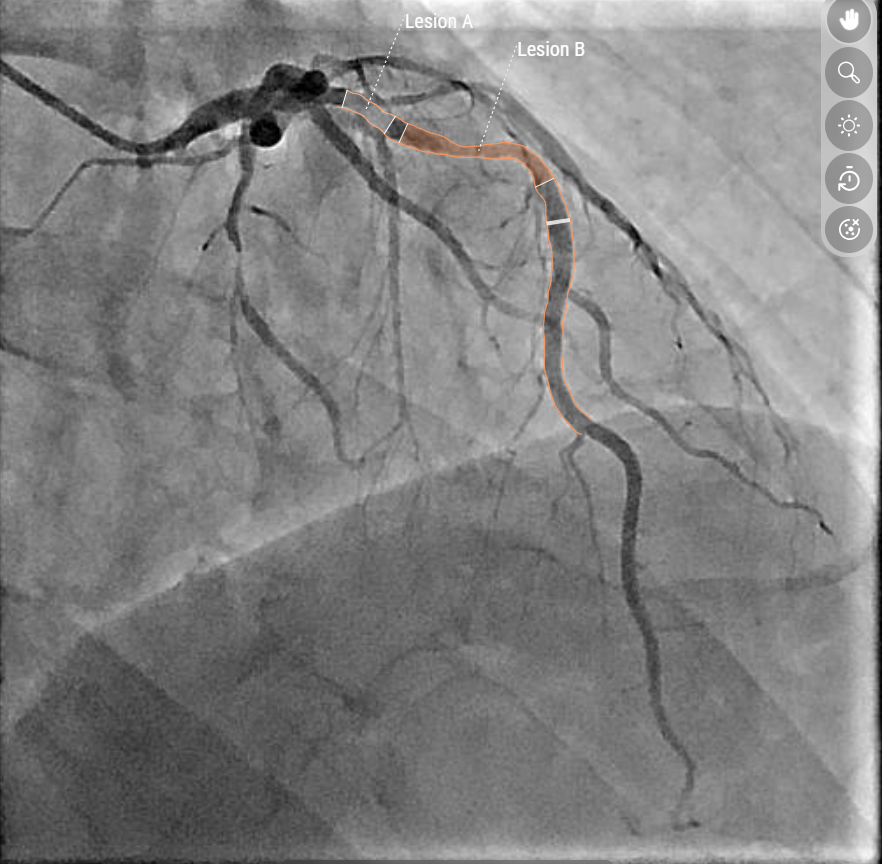

Die Darstellung der Herzkranzgefäße mittels Kontrastmittel und Katheter zählt seit vielen Jahren zum Goldstandard in der Diagnose und Behandlung von koronaren Herzerkrankungen. Bislang wurden die Angiografien von interventionellen Kardiologinnen und Kardiologen visuell analysiert. „Bei unklarer Relevanz einer Gefäßverengung – einer Stenose – konnte zusätzlich ein sogenannter Druckdraht eingebracht werden, um den Blutfluss zu messen“, erklärt Binder. Mit der neuen QFR-Software (Quantitative Flow Ratio) entfällt dieser invasive Schritt in vielen Fällen: „Die KI erkennt die Gefäße automatisiert, rekonstruiert sie dreidimensional und erstellt ein hämodynamisches Modell, das anzeigt, ob die Engstelle zu einer relevanten Durchblutungsstörung führt. Gleichzeitig analysiert die Software, ob und wie sich die Versorgungslage des Herzens durch eine eventuelle Gefäßaufweitung verbessern würde.“ So wird die Therapieentscheidung datenbasiert unterstützt und kann für jede Patientin und jeden Patienten individuell getroffen werden.

Links die klassische Darstellung, rechts das KI-Modell: Mit Hilfe der Software konnten zwei Engstellen an der Vorderwand des Herzens identifiziert und eine relevante Beeinträchtigung der Sauerstoffversorgung festgestellt werden. Das hämodynamische Modell zeigt: Eine gezielte Aufdehnung nur einer der beiden Stenosen reicht aus, um den Blutfluss wieder zu normalisieren.